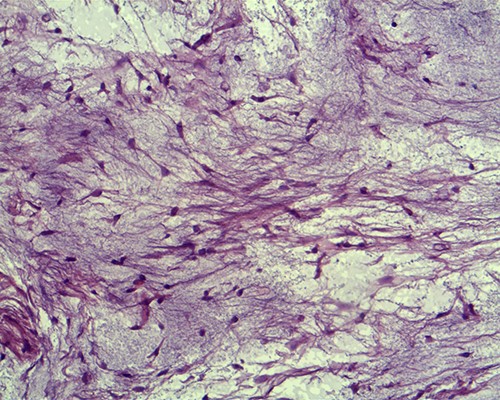

Histopathological examination of the surgical material revealed the lesion to be an IM. The tumour was surrounded by muscle fibres and composed of spindle- and stellate-shaped cells with small, hyperchromatic nuclei (Figs 3 and 4).

Tumour cells are small, spindle to stellate shaped with a pale indistinct cytoplasm and small hyperchromatic nuclei in which mitoses are rare (hematoxylin and eosin staining, ×20).

Macroscopically, IMs typically appear as oval, grey-white, gelatinous masses with a firm consistency [1, 3]. Microscopically, the lesions are usually hypocellular and hypovascular [1, 5, 13] and contain spindle- and stellate-shaped cells with small, hyperchromatic nuclei that are embedded within an abundant myxoid stroma [1, 6]. Generally, mitotic activity and pleomorphism are absent [1, 5]. In our case, the histopathological results were consistent with these typical findings of IMs.